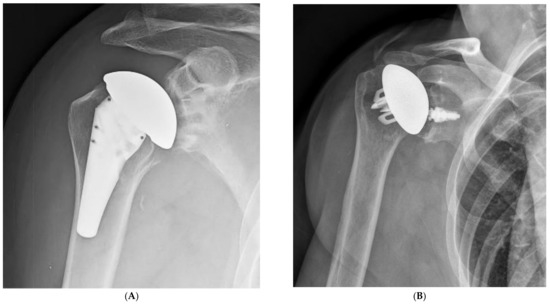

The preparation of the metaphysis for modern components that rely on peripheral fixation typically aims to place the component “bowl” so that it will leave 2–4 mm of cancellous bone between the component and the cortical rim of the metaphysis (Figure 8). A wider distance may be advantageous in patients with a stronger bone that does not require maximizing peripheral fixation. The guide pin for the reaming of the metaphysis may be centered using a trial humeral head or sizing discs.

Figure 8.

Primary component stability may be optimized by the implant fit at the periphery of the proximal humerus, within 2–4 mm of the cortical rim. (A), Sizing disk; (B), Trial; (C), Humeral component.